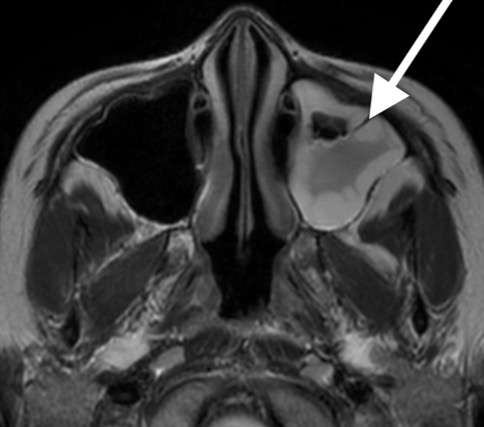

43歳女性、左の額の痛みで受診。頭部MRI検査で左前頭洞に炎症性変化を認めました。

このような鼻腔から離れた前頭洞炎の場合には、鼻水や鼻づまりはない事があります。